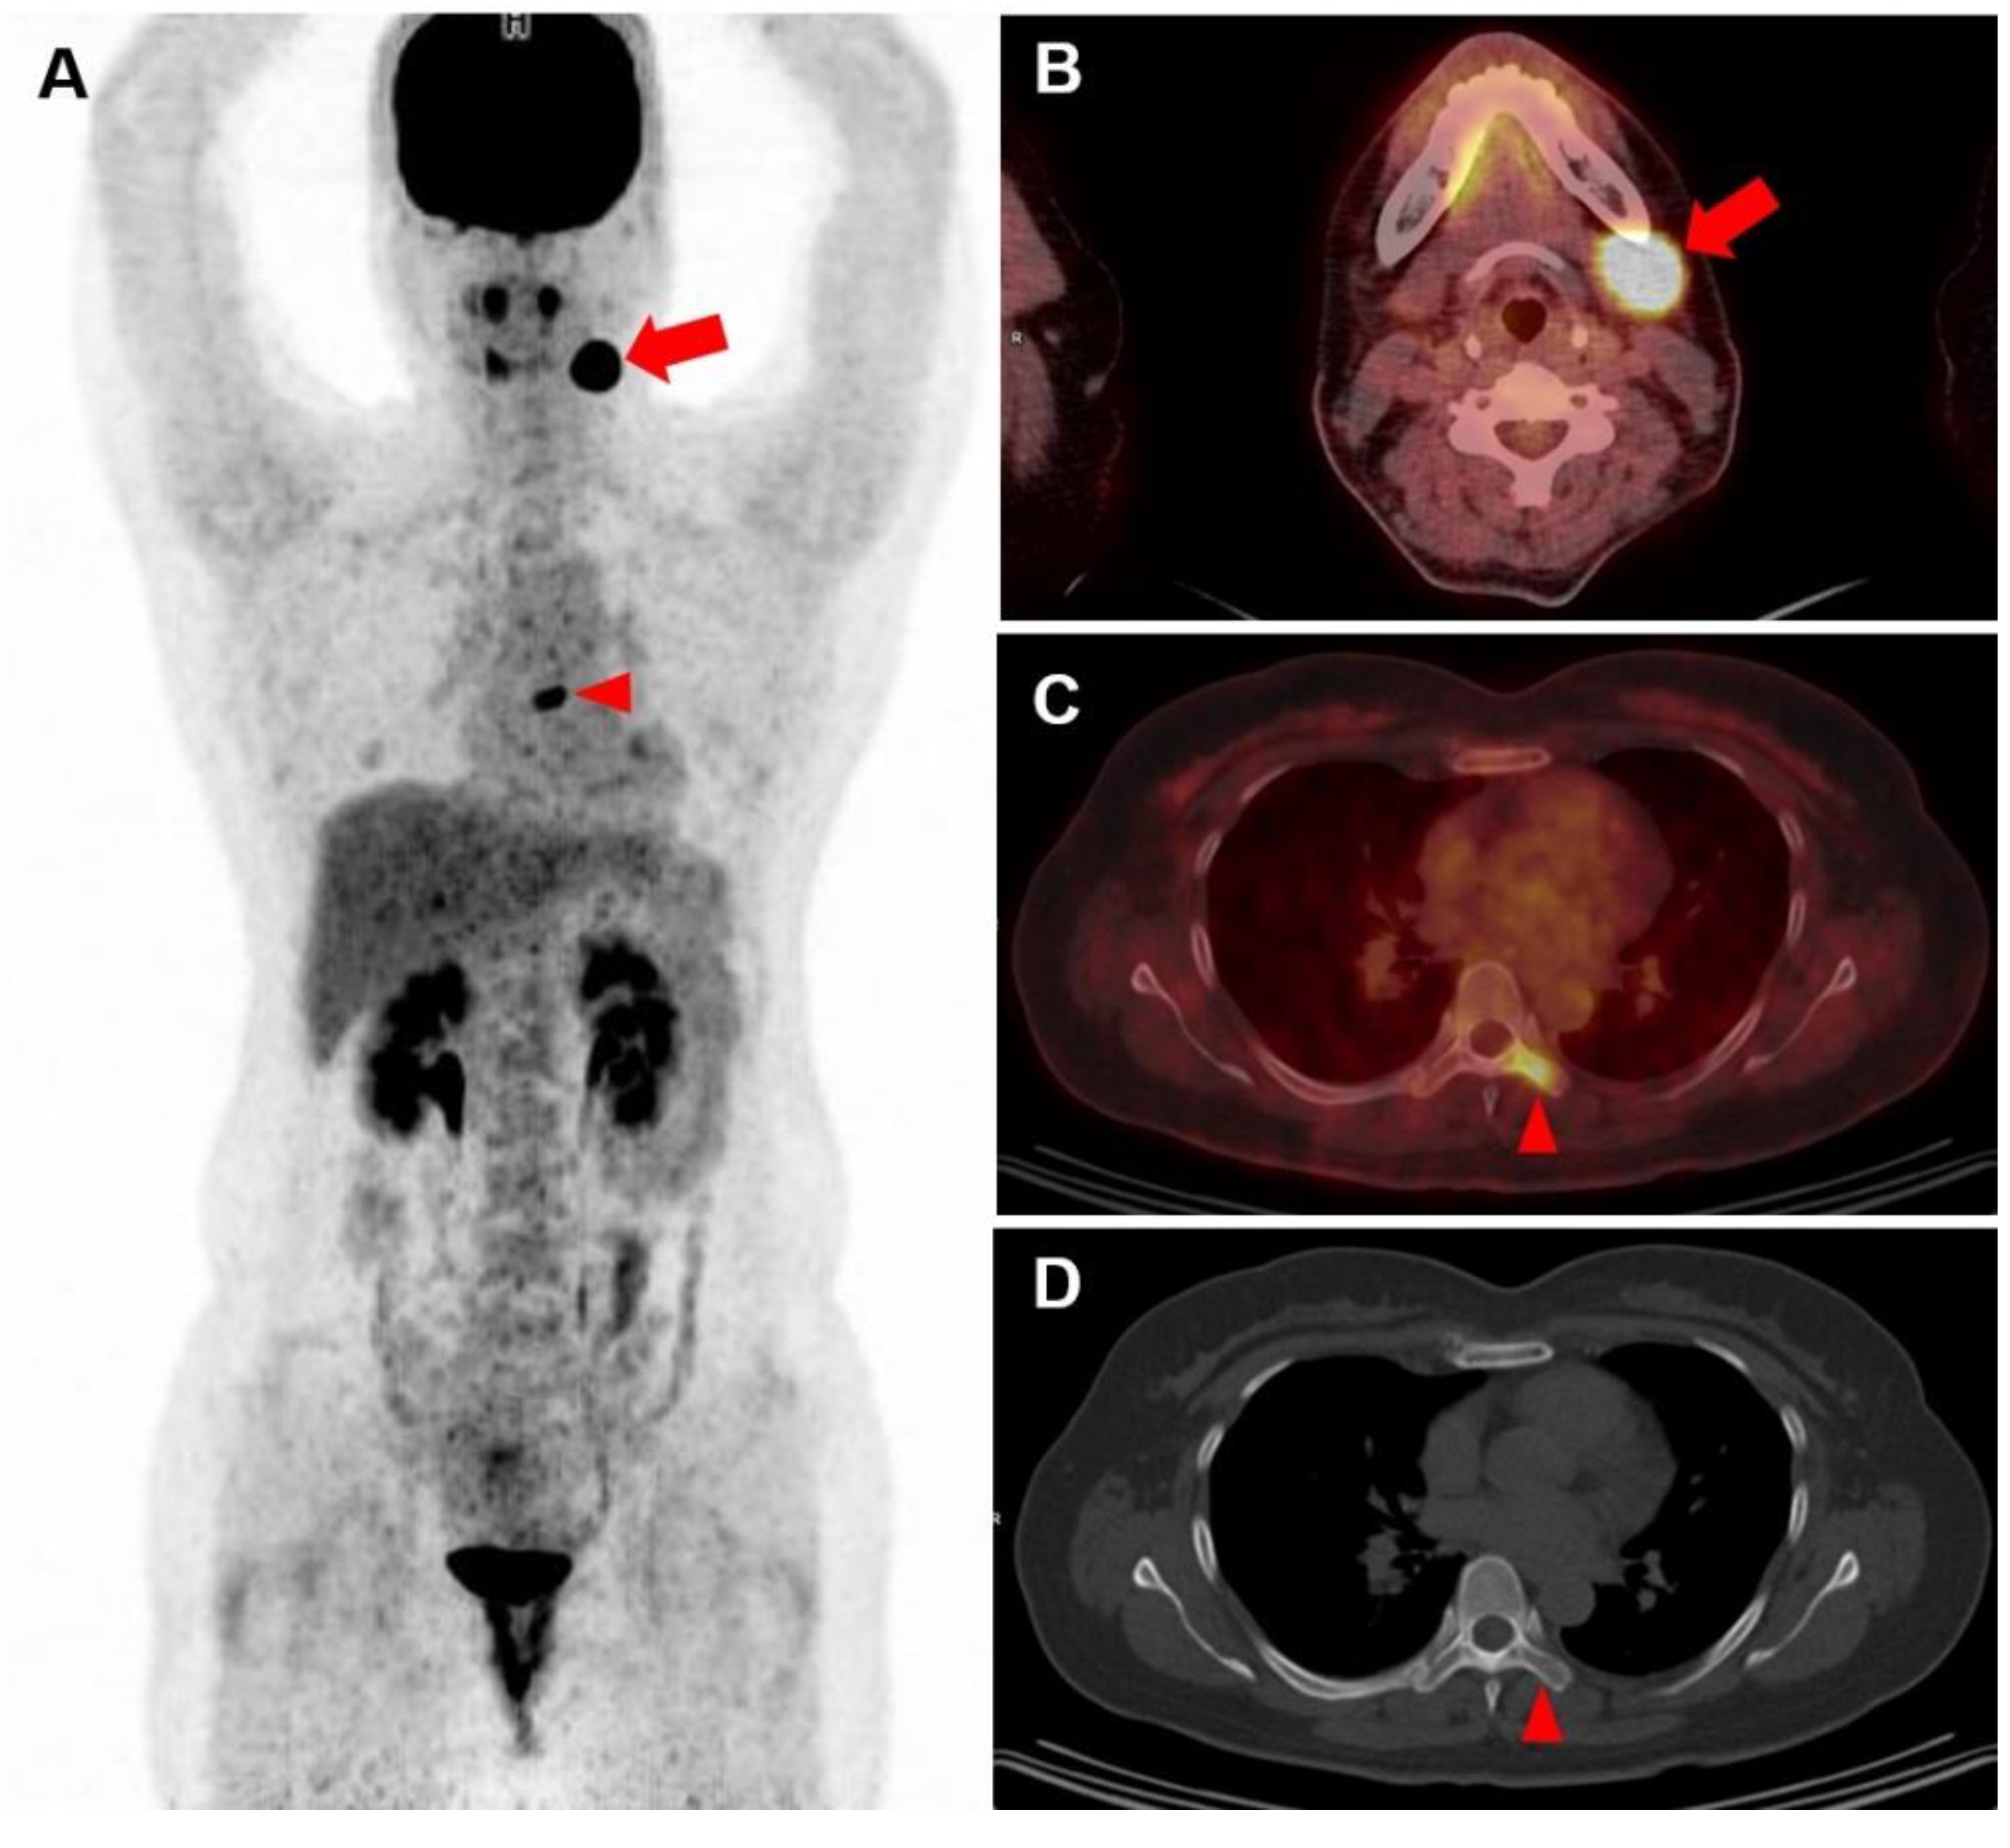

3.2. Visual Analysis of FDG PET/CT Images